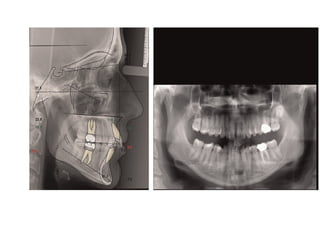

Successful orthodontic therapy of an adult female treated

bymandibula central incisor extraction

The patient presented a skeletal Class I with

normodivergent facial pattern, Class II subdivision dental

relationship, extremely deep Curve of Spee and severe

overbite.

Moreover, during the treatment, the upper left first molar

does not respond to orthodontic forces due to tooth

ankylosis, augmenting the

difficulty of this case.

Despite this, a good occlusal relationship on both sites and

an optimal extraoral outcome have been achieved after a

26-months therapy.

Improved smile and lip competency

Partial loss of lower papillae, triangular shape of

lower incisors

Root paralleling without resorption of anteriors

despite considerable intrusion of lower incisors

Reduction in lip protrusion This complex case highlights how

accurate diagnosis, a critical

overview of treatment and good patient compliance are indispensable

factors for achieving good outcomes

TREATMENT RSULTS